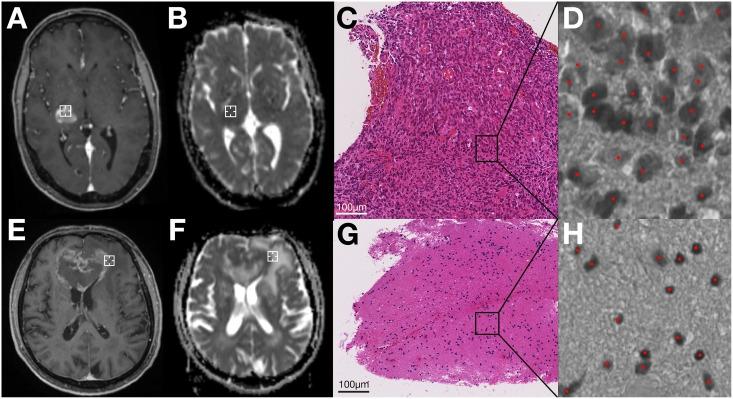

Thirty-seven patients with newly diagnosed glioblastomas were enrolled in this study. ADC maps were acquired preoperatively at 3T and coregistered to the intraoperative MRI that contained the coordinates of the biopsy trajectory. 561 biopsy specimens were obtained; corresponding cellularity was calculated by semi-automatic nuclei counting and correlated to the respective preoperative ADC values along the stereotactic biopsy trajectory which included areas of T1-contrast-enhancement and necrosis.